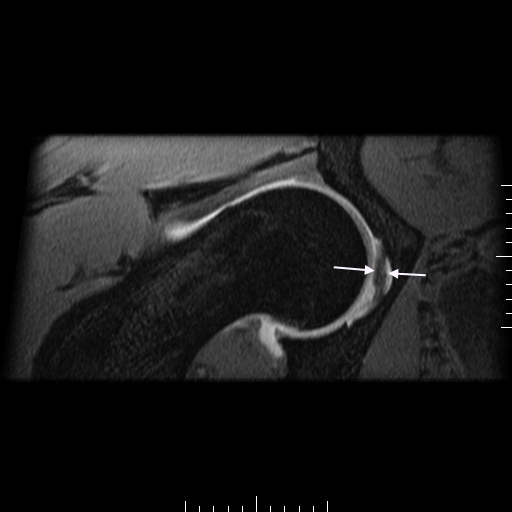

21 year old male with hip pain. Mild FAI on arthrogram with small bump and small anterior labral tear. Also, an accesory ligamentum plica although they can be symtomatic. In figure 3 the long arrow points to the true ligamentum, the short to the accessory ligamentum. In figures 1 and 4 the accessory is shown.

Hip Plica